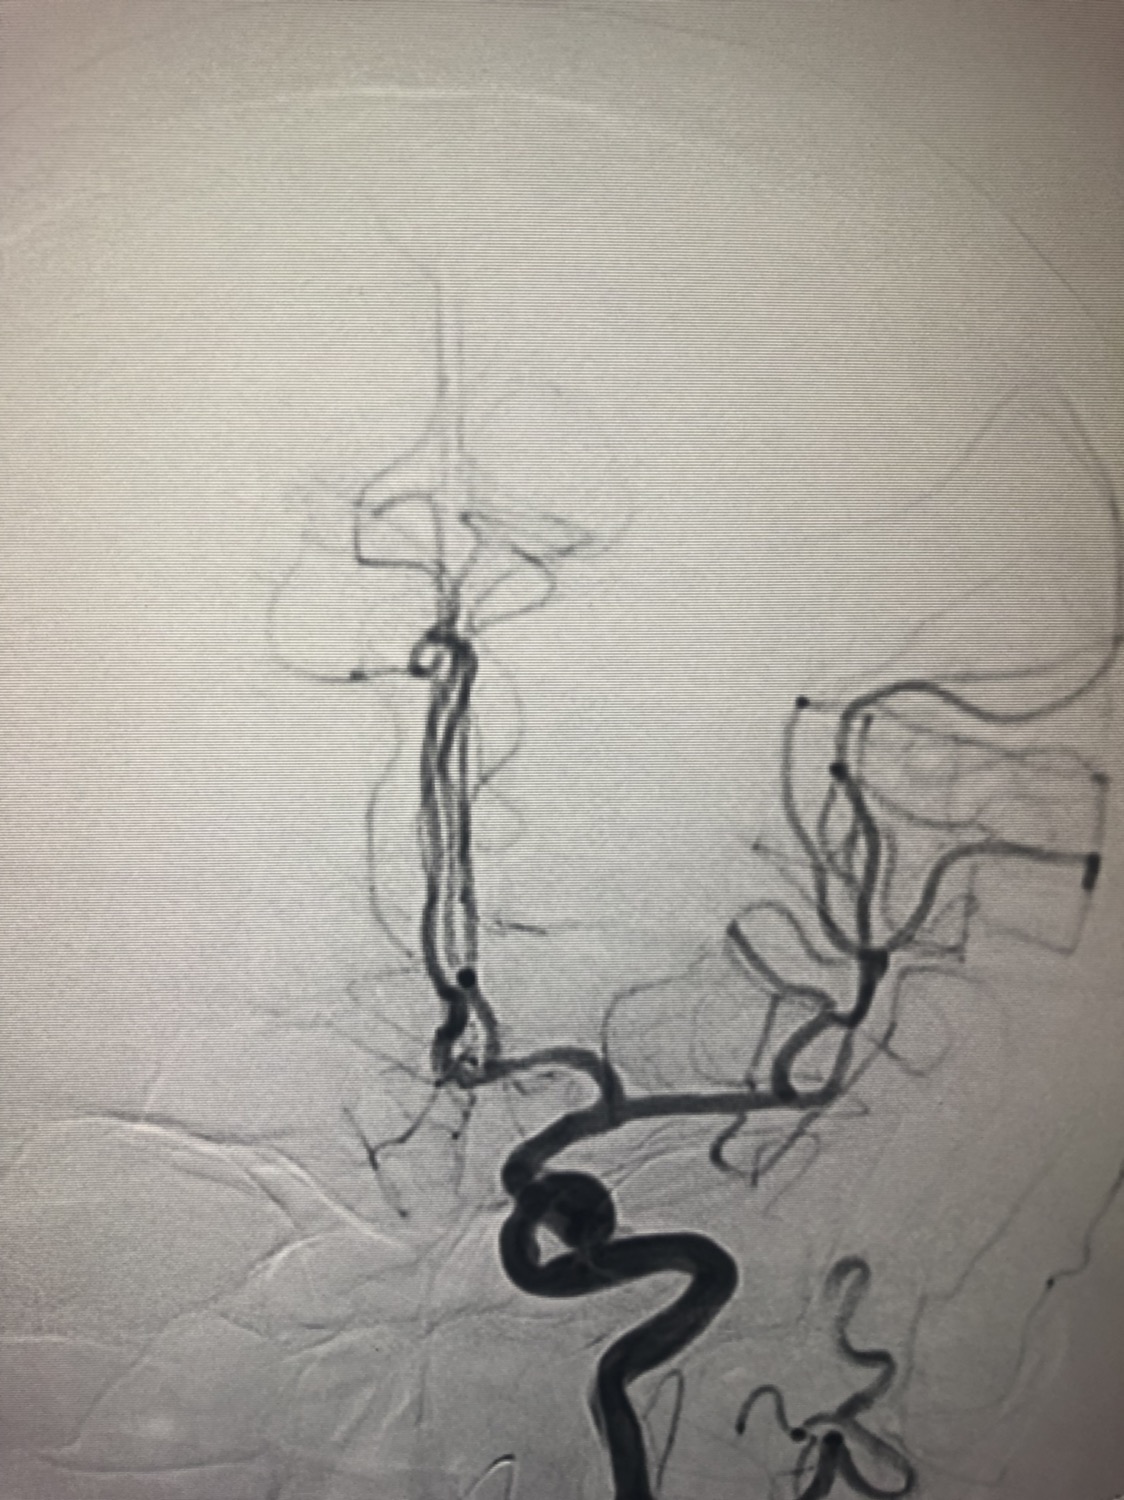

1周前房颤栓塞肱动脉,切开取栓后服用利伐沙班3天。突发偏瘫凝视3小时。上台看M3、A3血栓,国产普威森6f125cm抽吸导管高到位结合尼科3x20mm小支架,结合精细操作,m3和a3的血栓也可以轻松取出。不刺激血管。加造影射线16min两次取栓两个血管再通。

柔软的国产普威森微导管,高到位。

3x20mm的国产reco支架,适合分支血管取栓。